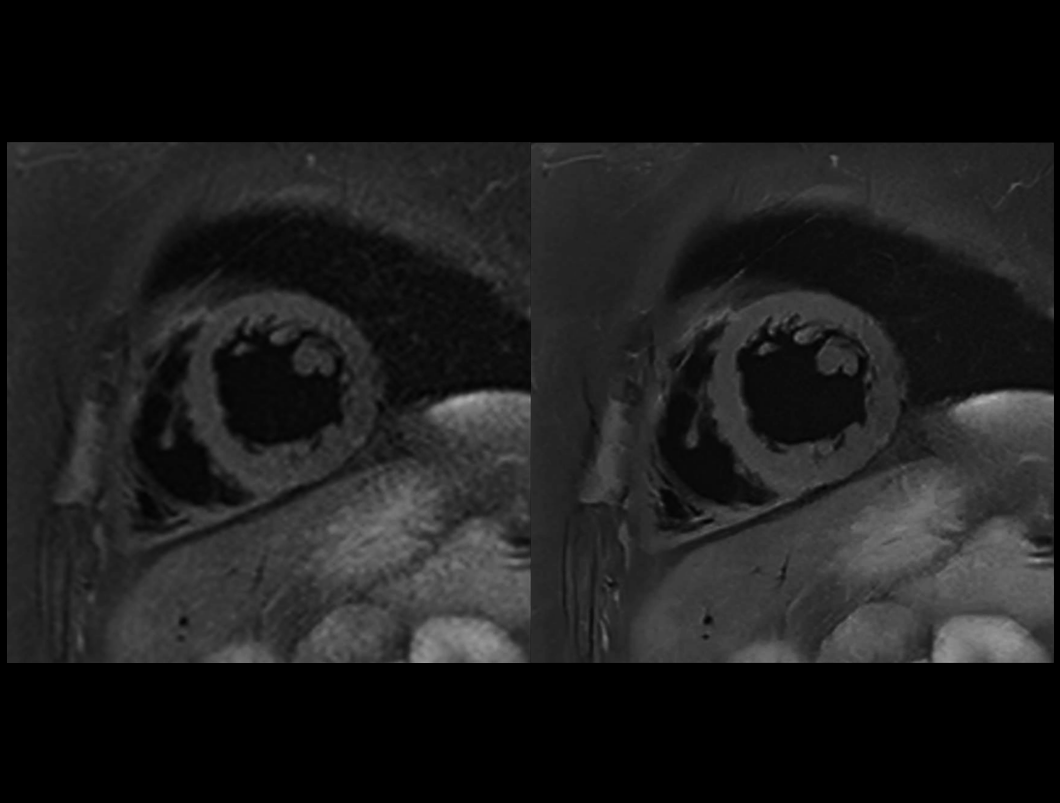

心脏 T2W DB SPAIR

常规成像 (9.4 sec) vs. uAIFI DeepRecon™ (9.4 sec)

0.78×0.78×4 mm3